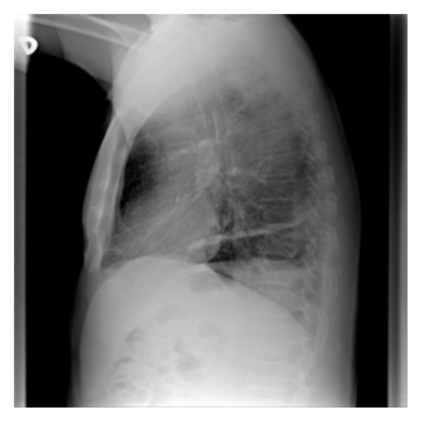

The evaluation of infectious disease processes on radiologic images is an important and challenging task in medical image analysis. Pulmonary infections can often be best imaged and evaluated through computed tomography (CT) scans, which are often not available in low-resource environments and difficult to obtain for critically ill patients. On the other hand, X-ray, a different type of imaging procedure, is inexpensive, often available at the bedside and more widely available, but offers a simpler, two dimensional image. We show that by relying on a model that learns to generate CT images from X-rays synthetically, we can improve the automatic disease classification accuracy and provide clinicians with a different look at the pulmonary disease process. Specifically, we investigate Tuberculosis (TB), a deadly bacterial infectious disease that predominantly affects the lungs, but also other organ systems. We show that relying on synthetically generated CT improves TB identification by 7.50% and distinguishes TB properties up to 12.16% better than the X-ray baseline.